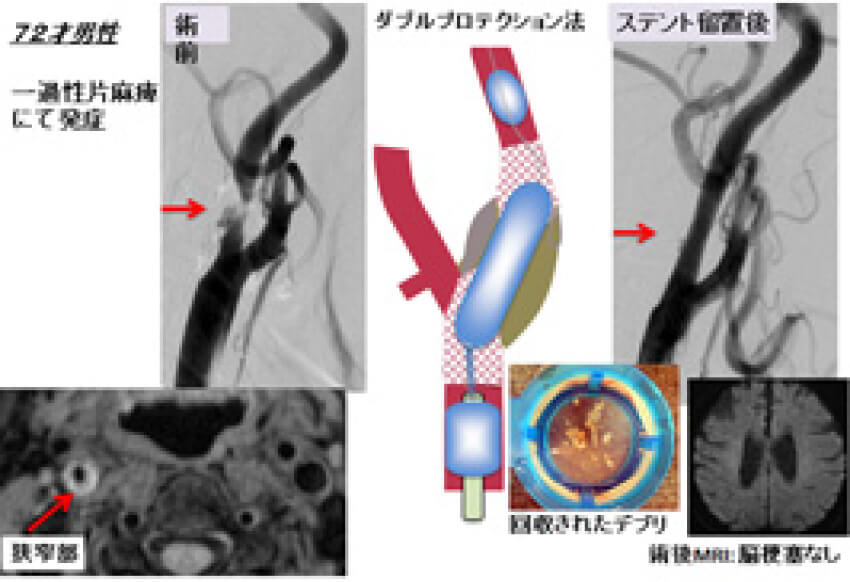

経橈骨動脈脳血管内治療(TRN)超入門:145本のWEB動画と。経橈骨動脈脳血管内治療(TRN)超入門:145本のWEB動画と。商品詳細ページ | メディカルブックセンター。茨城県筑西市産コシヒカリ10kg(令和6年度)5分つき。脳血管内手術 | 患者さまへ - 鳥取大学医学部 脳神経医科学講座。血管内治療 - 診療案内 - 愛知医科大学医学部 脳神経外科。鳥取大学医学部 器官制御外科学講座 心臓血管外科学分野 TOTTORI。血管内治療 - 診療案内 - 愛知医科大学医学部 脳神経外科。朝倉書店『内科学』(第12版)デジタル付録。超音波および神経刺激の小児アトラス-ガイド付き局所麻酔-第27章。。経橈骨動脈脳血管内治療(TRN)超入門:145本のWEB動画とイラストで学ぶ 難易度別テクニック&エッセンス\r\r購入後一読のみ。メジカルビュー社|脳神経外科|新NS NOW 11 Advanced脳血管内治療。\r書き込み、線引き、裁断なし。脳動静脈奇形に対する血管内治療 | 脳血管内治療学研究センター。\r目立った折れや汚れもなく美品だと思います。脳神経血管内治療科。